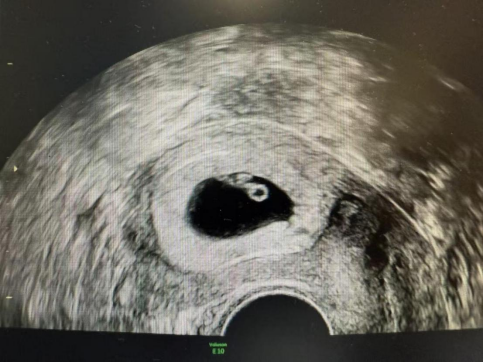

信任与专业,最终共同孕育了奇迹。移植后,验孕结果显示——成功妊娠!超声更清晰地看到了搏动的胎心管和健康的胎芽!